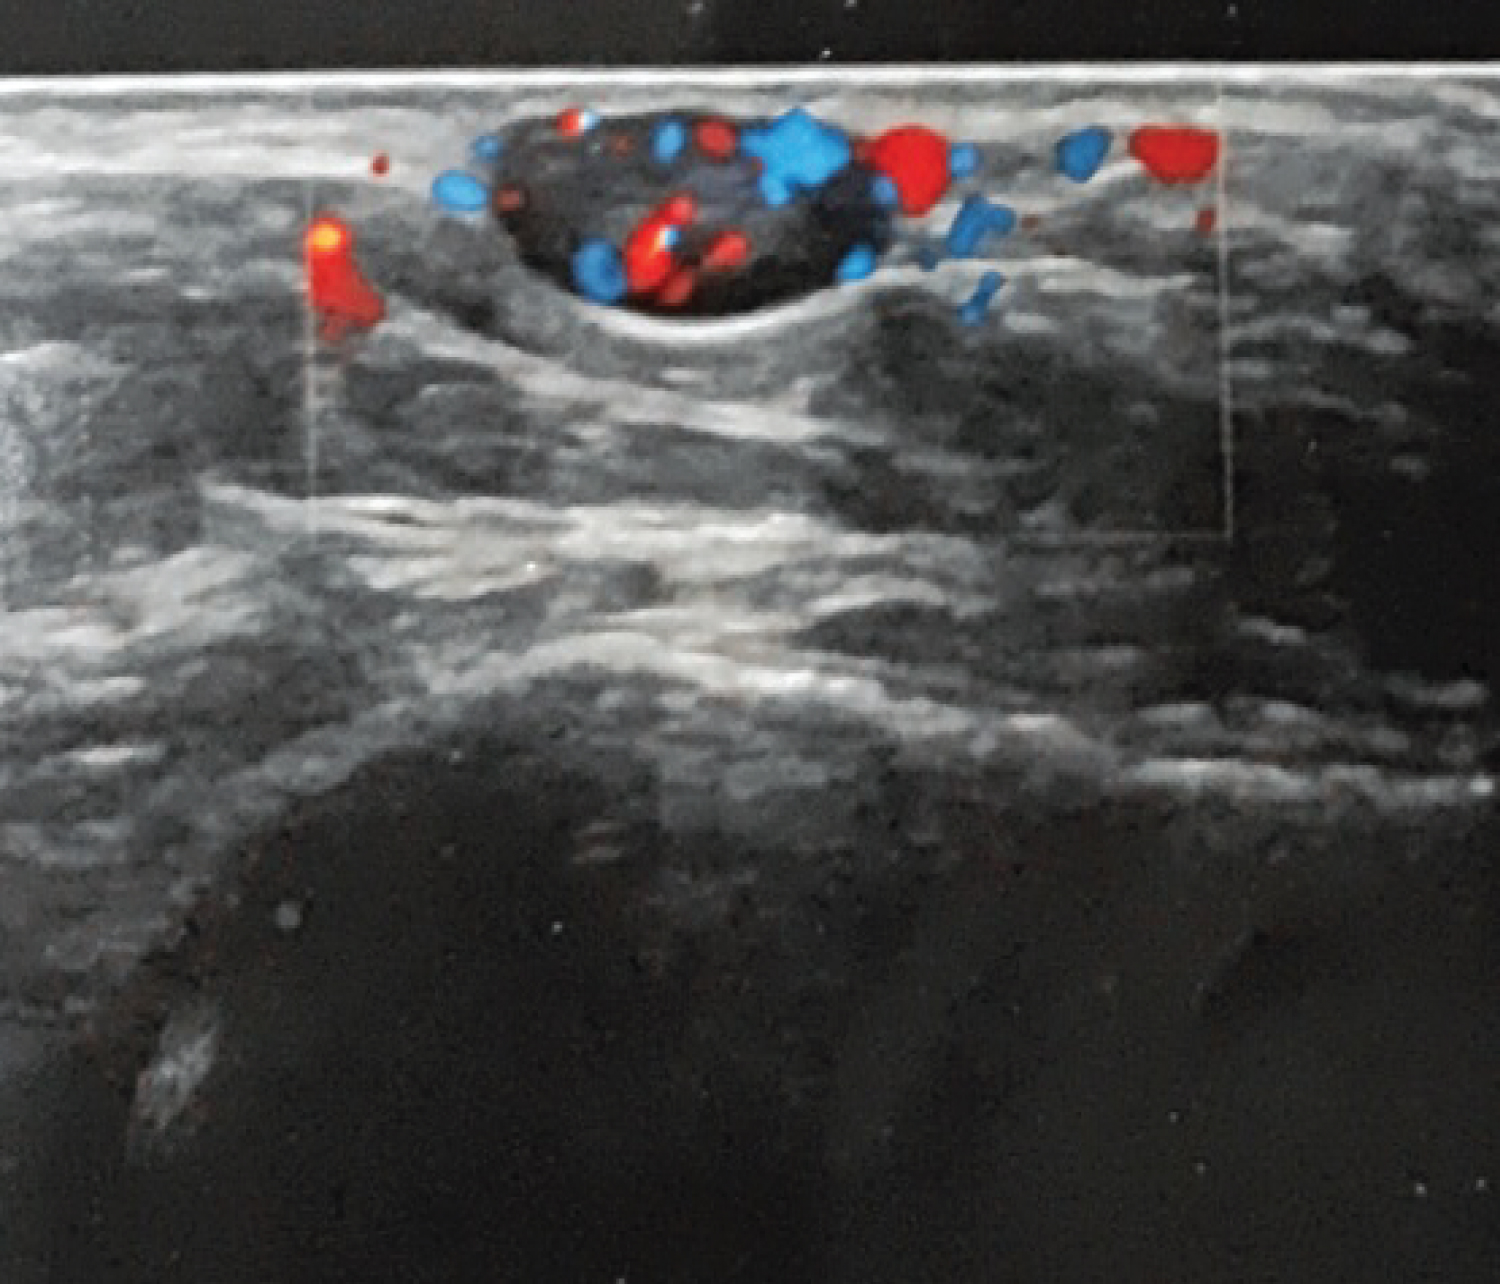

Ultrasounds results shows well-limited superficial ovoid subcutaneous nodule of the external side of the left ankle without septa or intralesional necrosis, hypervascularized by colour Doppler, evoking in first place a schwannoma (Figure 2 and Figure 3).

Figure 3: Significant peripheral and central vascularisation. View Figure 3